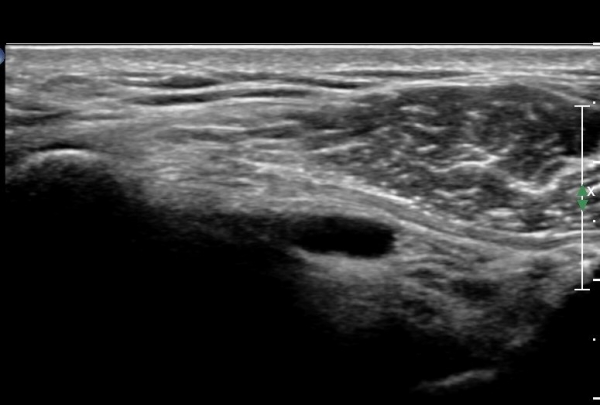

ÃÊÀ½ÆÄ °Ë»ç

¿À±¸µ¹±â°ßºÀÀδë Á¾´Ü¸é°Ë»ç¿¡¼­ ÀÎ´ë ½ÉÃþ¿¡ ¼ö¾×Àú·ù°¡ °üÂûµÊ(»çÁø 1, 2)

ÀÌ´Â Ãæµ¹ÁõÈıºÀ» ¾Ï½ÃÇÏ´Â ¼Ò°ßÀÓ.